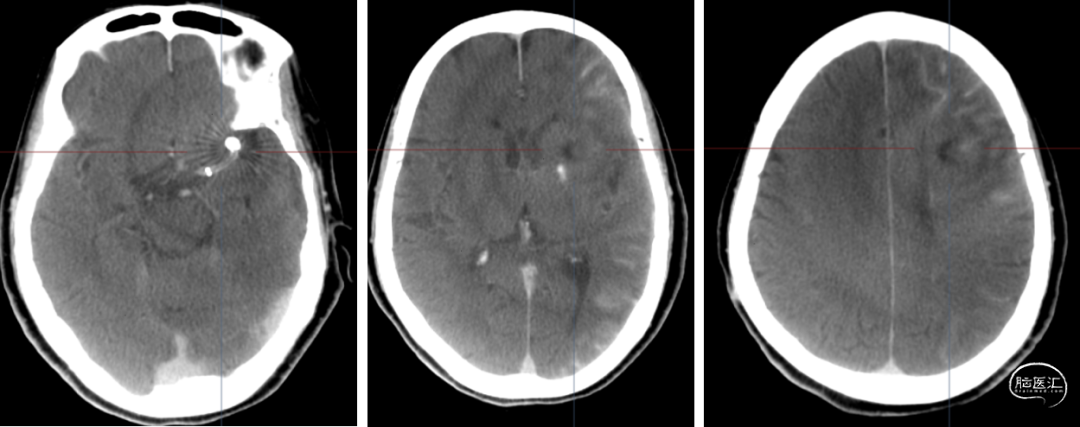

头颅CT

术前

术后第一天

4个月复查,停单抗

8个月复查

停单抗